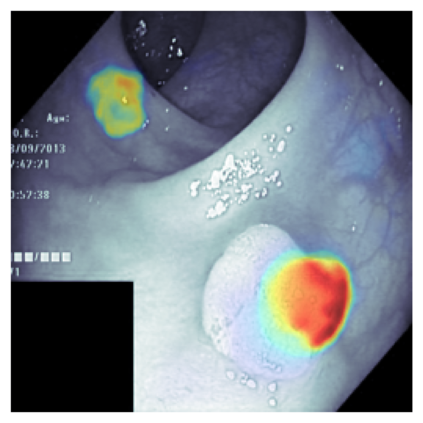

The sigmoid activation is the standard output activation function in binary classification and segmentation with neural networks. Still, there exist a variety of other potential output activation functions, which may lead to improved results in medical image segmentation. In this work, we consider how the asymptotic behavior of different output activation and loss functions affects the prediction probabilities and the corresponding segmentation errors. For cross entropy, we show that a faster rate of change of the activation function correlates with better predictions, while a slower rate of change can improve the calibration of probabilities. For dice loss, we found that the arctangent activation function is superior to the sigmoid function. Furthermore, we provide a test space for arbitrary output activation functions in the area of medical image segmentation. We tested seven activation functions in combination with three loss functions on four different medical image segmentation tasks to provide a classification of which function is best suited in this application scenario.